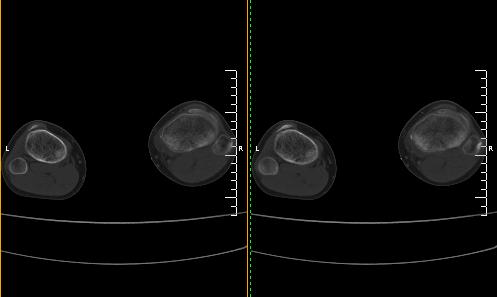

标题: CT19091:右胫骨近段骨性突出.

男,15岁,右胫骨近段软组织肿胀,下肢疼痛10左右.

右胫骨近端内侧骨性突起,皮质连续,骨质结构正常,首先考虑胫骨骨软骨瘤,随访观察。

右胫骨上端内侧骨软骨瘤可能性大。